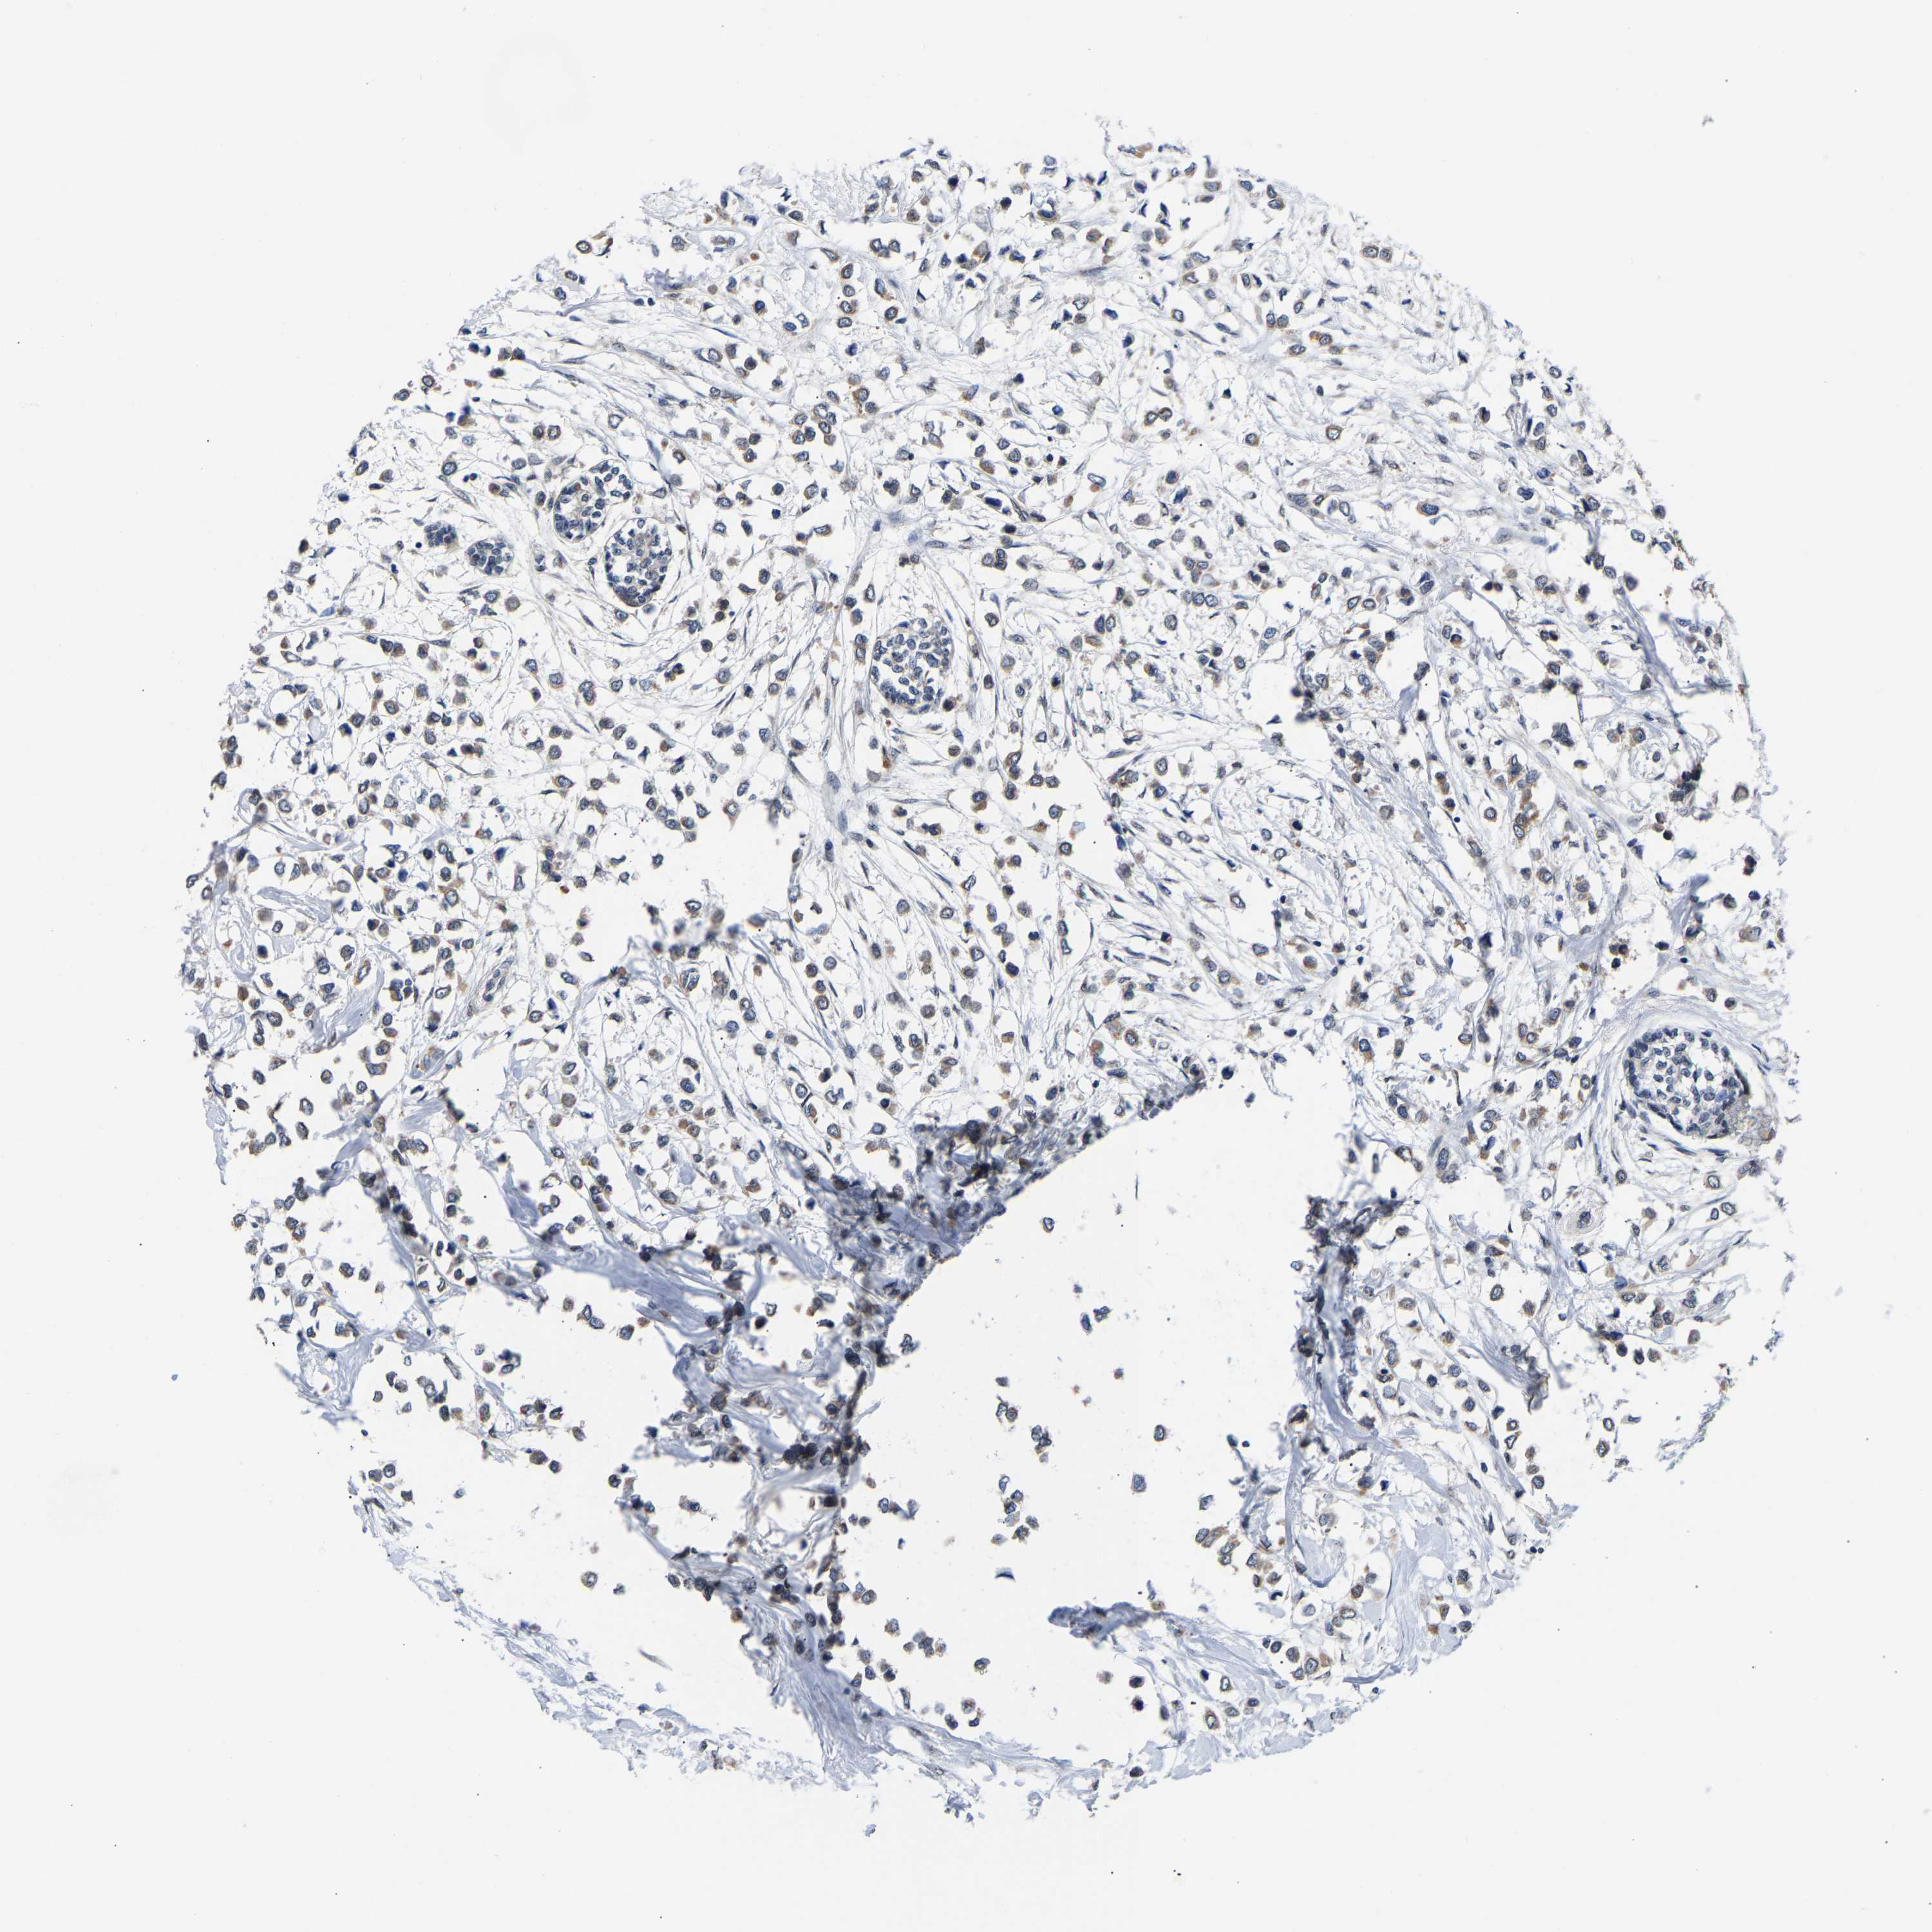

CANCER BREAST CANCER Show tissue menu

BRCA TCGA BRCA VALIDATION PROTEIN EXPRESSION